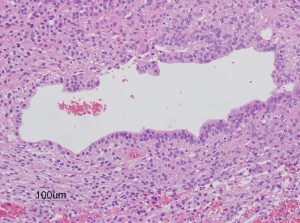

第4脳室床に発生した典型的な上衣腫 EPN-PFA の画像です。水頭症になって,頭痛と嘔吐,意識障害で発症しました。典型的なMRI画像と病理所見です。MRIでは第4脳室からマジャンディー孔を越えて脊髄背側まで長く腫瘍が伸びています。腫瘍内部に小さなのう胞が複数みられます。病理像では,血管周囲に細胞核がない無核野が認められます。血管周囲に伸びた繊細な単極性突起が集まった領域です。これは,血管周囲偽ロゼット perivascular pseudorosette という上衣腫に特徴的な病理所見です。

摘出した標本のHE染色です。左側ではperivascular pseudorosette(血管周囲の無核野)がみられ,右側ではependymal tube (ependymal canal) が認められます。

左がGFAP染色、右がMIB-1(Ki-67)染色です。 GFAPは腫瘍血管の周囲の無核野に強陽性です。MIB-1 labelling index が1%以下であり,この上衣腫の増殖能が極めて低いことを示しています。このような高分化型で増殖能の低い上衣腫は脊髄髄内には多いのですが,脳では珍しいものです。ovex中心上衣腫にみられます。